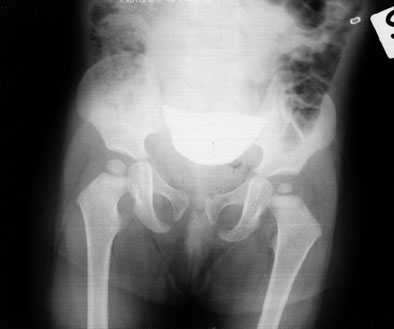

Con l'esame clinico l'ortopedico conferma, alla manovra di Ortolani, la risalita dell'anca, la riducibilità dell'anca sinistra, la dismetria degli arti inferiori e l'importante asimmetria delle pliche. Eseguito un radiogramma del bacino per anche, viene confermata una lussazione dell'anca sinistra, con un tetto acetabolare assolutamente insufficiente.